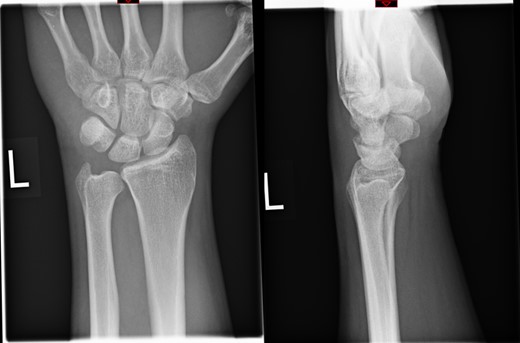

The X-rays of the patient was later reviewed by the duty radiologist and reported as a suspected dislocation of the pisiform bone, Fig. 1. Therefore the patient was recalled to the trauma clinic after three days. He was reassessed and a further three dimensional scan of the wrist was arranged. The CT scan demonstrated distal dislocation of the pisiform which appeared to lie in a ‘locked’ position beyond the distal triquetrum, Fig. 2.